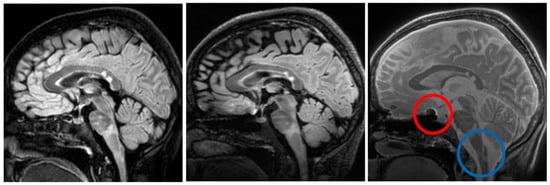

Figure 8 shows Silent MTR maps from a healthy volunteer (left) and a patient with Multiple Sclerosis (right). The MTR map of the healthy volunteer shows some contrast between grey and white matter. The MTR of the white matter is fairly uniform across the brain of the healthy volunteer. The Silent MTR map of the MS patient shows visually apparent increases in MTR peri-ventricularly and in the left temporal lobe.

Figure 8. Silent MTR in healthy control (left) and MS patient (right). Silent MTR is increased in region of left temporal lobe and peri-ventricularly. ROI’s used to make MTR measures are shown in red.

Regions of interest were drawn in equivalent locations of the superior temporal lobe in the MS patient and the control.

The MS patient ROI had mean MTR 37.5% and standard deviation 4% (percentage units). The control ROI had mean MTR 28.6% and standard deviation 1.5%.